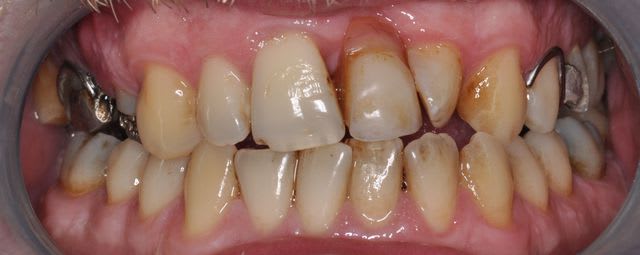

Merci Bob, je viens de voir ton post, c'est très sympa. Malheureusement, sauf erreur de ma part, il s'agit d'un cas de fluorose légère et non de MIH. Belles photos en tout cas.

Salut, désolé de ne pas avoir trouvé ce que tu cherches, peux-tu m'expliquer comment tu différencies ces lésions? ( lorsque j'ai vu ce jeune patient cela m'avait l'air de ressembler à ce que tu recherches donc j'ai pris qq clichés)

Pour les MIH :

- Opacités délimités, contours nets

- Couleur blanc-jaune à brun, "crème" en général

- Forme des taches

- Affecte au moins une première molaire permanente et dans 75% des cas une ou plusieurs incisives permanentes. Très rarement d'autres dents (pointes canines ou secondes molaires)

- Atteintes asymétriques (on peut voir une 16 très atteinte, une 36 modérément atteinte, une 26 intacte)

Pour les fluoroses :

- Opacités à contours flous

- Blanc dans les cas légers (les plus courants en France), jaune-brun à brun dans les cas modérés ou sévères.

- Forme des stries qui suivent les périkymaties mais ces stries confluent souvent en taches ou en bandeaux

- Affecte toutes les dents d'une denture

- Atteintes symétriques Gauche/Droite

Encore merci à toi pour le temps que tu as pris.

1ère photo : fluorose légère

2ème : MIH